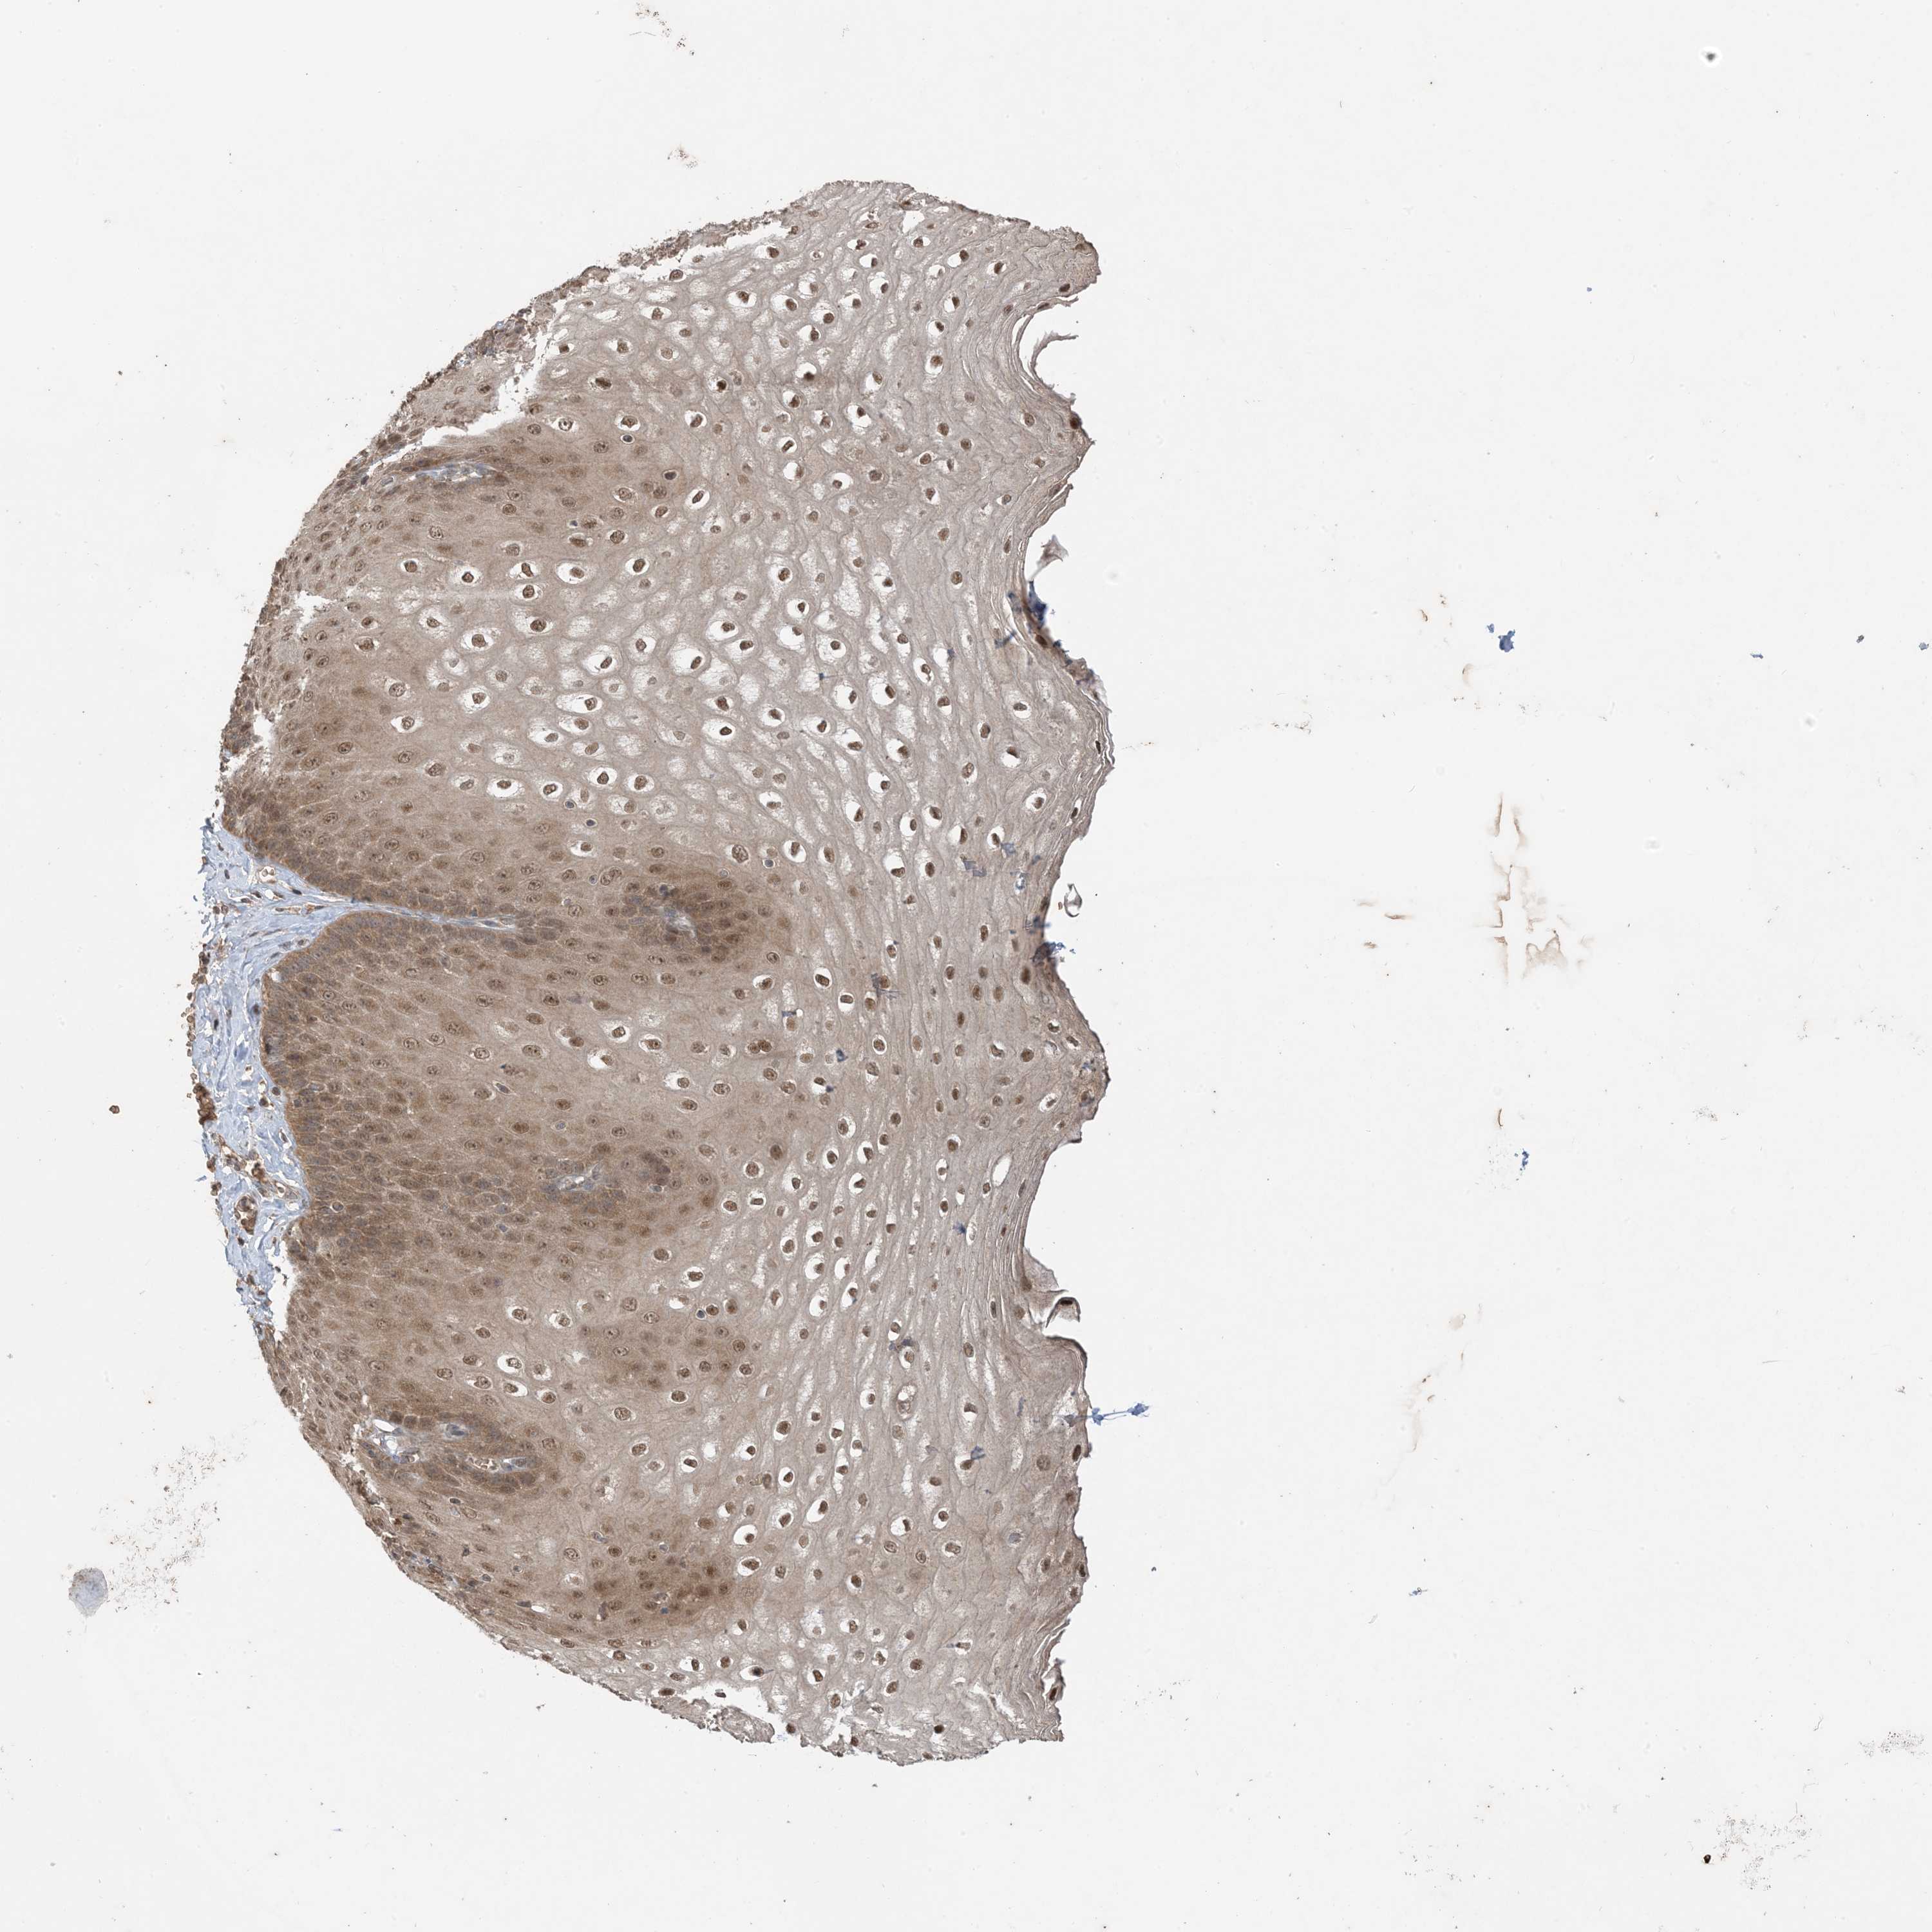

ESOPHAGUS - Antibody stainingi

Antibody staining in the annotated cell types in the current human tissue is reported as not detected, low, medium, or high, based on conventional immunohistochemistry profiling in selected tissues. This score is based on the combination of the staining intensity and fraction of stained cells.

Each image is clickable and will lead to virtual microscopy that enables deeper exploration of all samples and also displays staining intensity scores, fraction scores and subcellular localization as well as patient and tissue information for each sample.

Antibody HPA032057

Squamous epithelial cells Medium